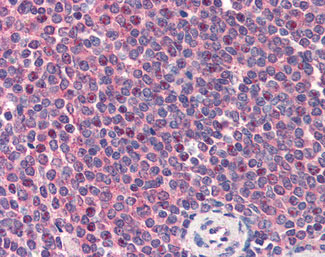

Anti-CARD11 antibody IHC of human spleen. |